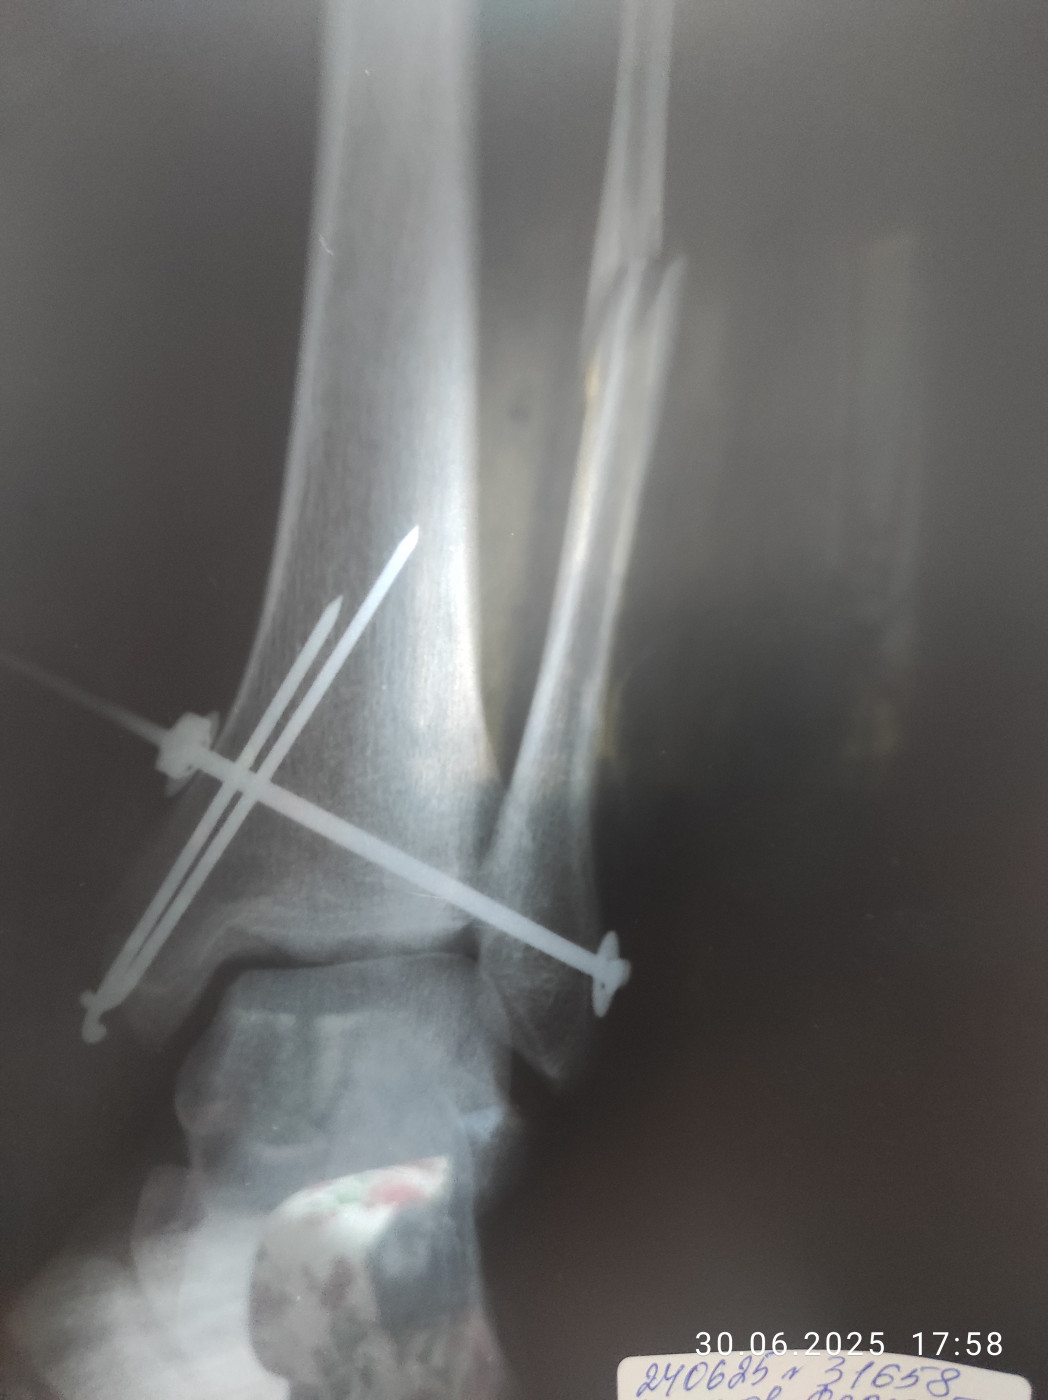

Срослась ли кость?   1 ответ

Добрый день!В 2023 году был получен оскольчатый перелом большеберцовой кости со смещением.На сегодняшний день сохраняются боль и отечность.Мнения врачей расходятся

26 июл 2025 14:45